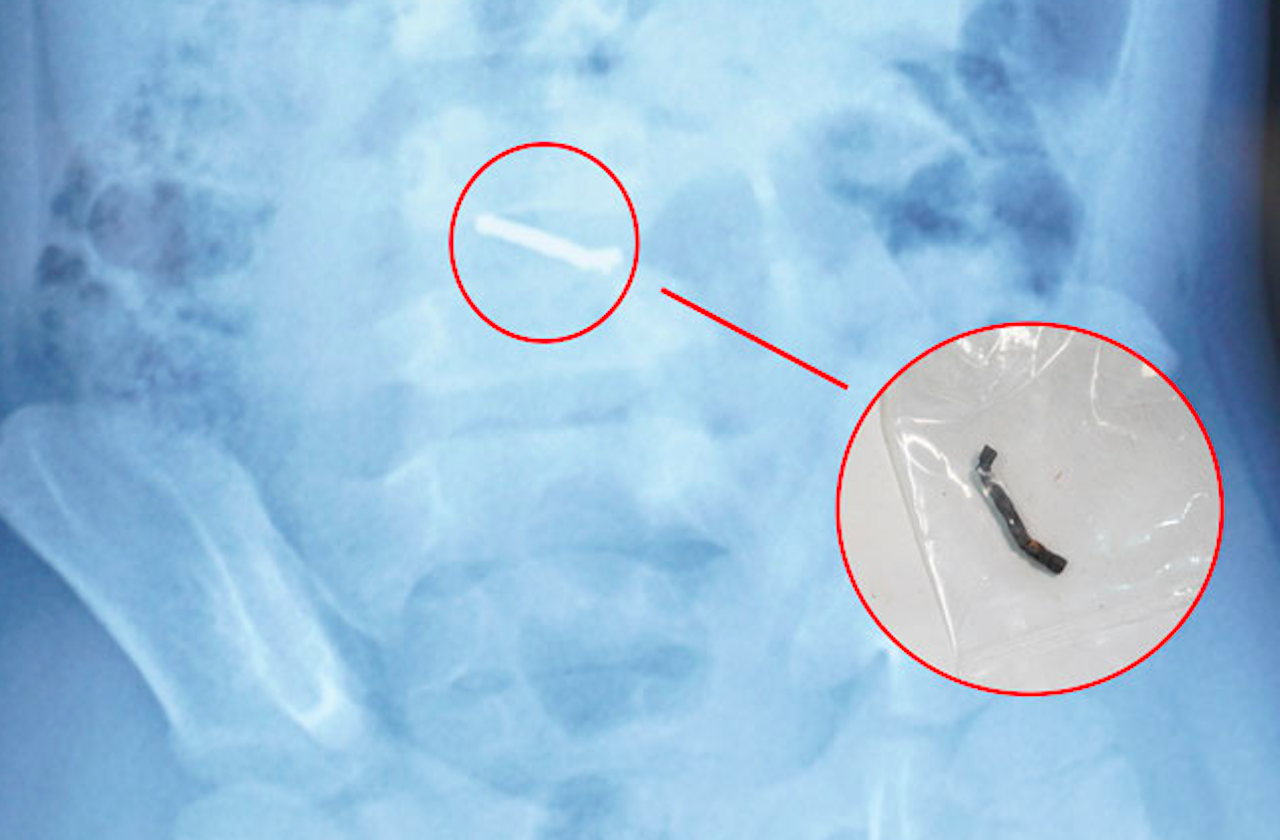

Hình ảnh nam châm dính thành chuỗi trong ổ bụng bệnh nhi. Ảnh: BVCC.

Thanh nam châm dính chặt sau khi được các bác sĩ lấy ra từ bụng bệnh nhi. Ảnh: BVCC.

Từ thông tin gia đình cung cấp về loại đồ chơi có các viên nam châm nhỏ có thể hút vào nhau, các bác sĩ chẩn đoán trẻ đã nuốt phải nhiều viên nam châm trong nhiều thời điểm. Sau khi xác định dị vật có từ tính và không thể tự đào thải ra ngoài, các bác sĩ đã tiến hành phẫu thuật cho trẻ.

Trong quá trình phẫu thuật, các bác sĩ phát hiện nhiều viên nam châm nhỏ dính vào nhau thành một chuỗi, gây thủng ruột. Các bác sĩ phẫu thuật đã tiến hành lấy dị vật, khâu lỗ thủng và đặt dẫn lưu. Sau 4 ngày, bệnh nhi đã sinh hoạt bình thường, bắt đầu được tập ăn trở lại và dự kiến sẽ được ra viện trong một vài ngày tới.